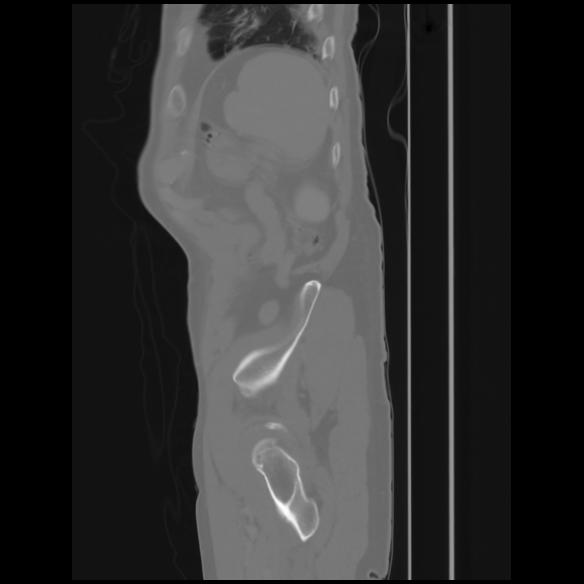

7 CUERPO,CE,Sagittal,3.000,CUERPO,Sagittal,